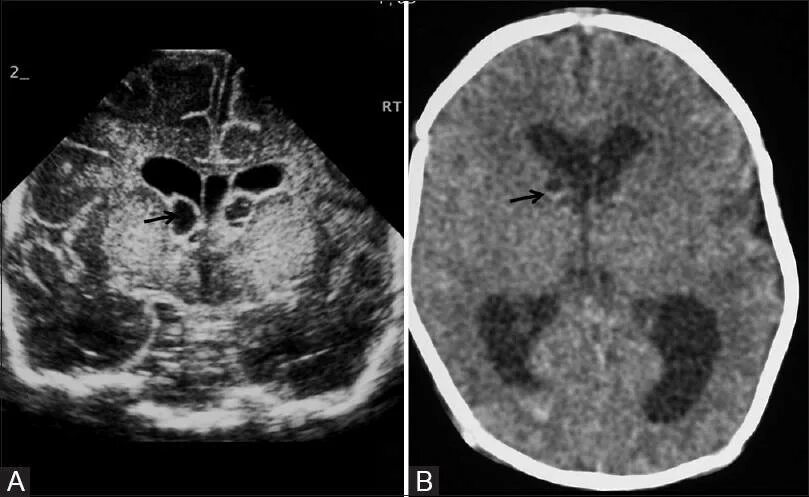

Кровоизлияние в мозг у новорожденного степени